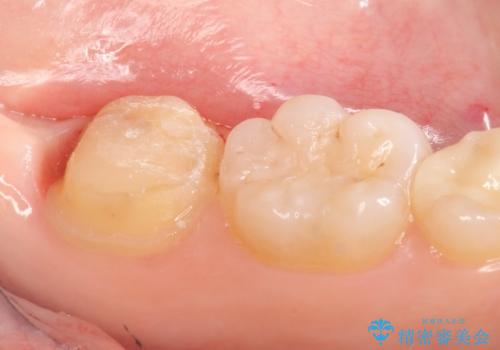

- 左下7の銀歯を白くしたいといらっしゃった方の症例です。

その後歯茎の治りを待ちポケットが正常値であることを確認後、オールセラミッククラウンによる補綴を行いました。

今回用いたオールセラミッククラウンはジルコニアフレームという白い素材の上にセラミックを盛っているため、審美性が非常に高いのが特徴です。

また、ジルコニアは人工ダイヤモンドの材料にも使われているほど高い強度を持っており、そのためオールセラミッククラウンは審美性だけでなく、奥歯やブリッジの補綴も可能とするクラウンです。